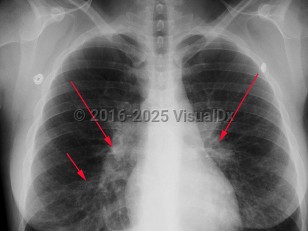

Mycoplasma pneumonia

Mycoplasma pneumonia, also called atypical pneumonia and "walking pneumonia," is a community-acquired pneumonia caused by Mycoplasma pneumoniae. Mycoplasma are pleomorphic, filamentous bacteria that lack a cell wall, are of a smaller size, and possess different genetic features than other bacteria. Of all the Mycoplasma spp isolated from the respiratory tract, M pneumoniae is the most frequent cause of human disease.

Mycoplasma pneumoniae is a common cause of pneumonia and may be responsible for up to 20% of all pneumonias in the general population and 30%-50% of pneumonias in specific closed populations such as those in military barracks and on college campuses. Infection is most common in those younger than 20, although it is seen in all age groups. The disease is seen throughout the year, with a slight increase in incidence in the fall and winter.